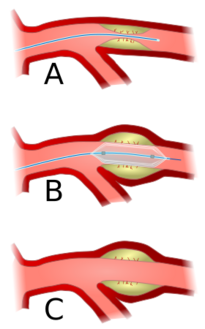

Angioplasty (pictured) and stenting are two endovascular treatments employed by the vascular surgeon.